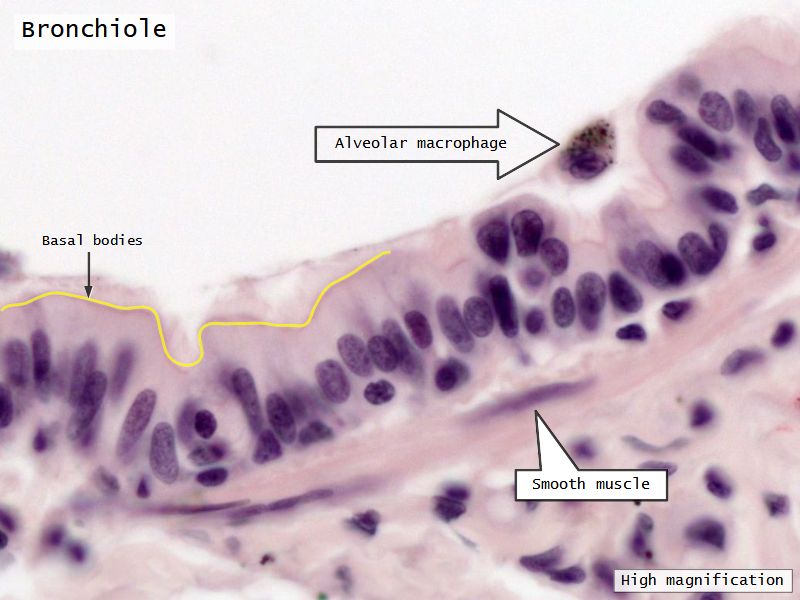

Respiratory epithelium

- Pseudostratified

- Ciliated

- Columnar

- Ciliated columnar cells

- Non-ciliated columnar cells

- Goblet cells

- Basal cells